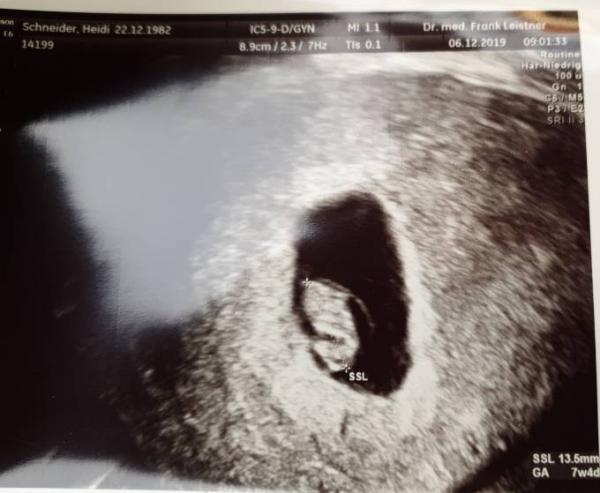

So - heute hatte ich nun auch meinen ersten Ultraschall Termin. Das Herzchen schlägt kräftig und es ist auch nur eins . Ich hatte laut Periode den 16.7. als ET ausgerechnet, aber der Arzt hat es vermessen und als ET nun 26.7. errechnet. Aber da mache ich mich jetzt nicht verrückt. Das Herzchen hat so fleißig gewummert da wird auch alles gut gehen.

Bild zu Unser Herzchen schlägt auch kräftig. - Forum für Juli - Mamis

Hey du, gratuliere! Wenn ich aber auf deinem Ultraschallbild schaue, steht da was von ssw 7+4, soweit bin ich auch genau und mein ET ist der 20. Juli. Dann wärst du ja gar nicht soweit vom 16. Juli entfernt. Wie kommt dein Arzt denn auf den 26. Juli?